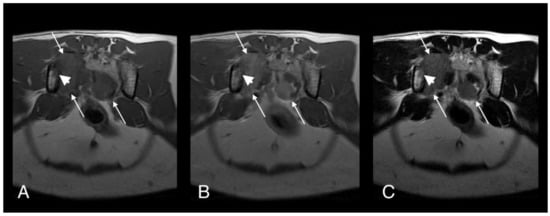

- Bennett, A.D.; Lalor, S.; Schwarz, T.; Gunn-Moore, D.A. Radiographic findings in cats with mycobacterial infections. J. Feline Med. Surg. 2011, 13, 718–724. [Google Scholar] [CrossRef] [PubMed]

- Major, A.; Holmes, A.; Warren-Smith, C.; Lalor, S.; Littler, R.; Schwarz, T.; Gunn-Moore, D. Computed tomographic findings in cats with mycobacterial infection. J. Feline Med. Surg. 2016, 18, 510–517. [Google Scholar] [CrossRef]

- Major, A.; O’Halloran, C.; Holmes, A.; Lalor, S.; Littler, R.; Spence, S.; Schwarz, T.; Gunn-Moore, D. Use of computed tomography imaging during long-term follow-up on nine feline tuberculosis cases. J. Feline Med. Surg. 2018, 20, 189–199. [Google Scholar] [CrossRef]

- Lalor, S.M.; Clark, S.; Pink, J.; Parry, A.; Scurrell, E.; Fitzpatrick, N.; Watson, F.; O’Halloran, C.; Gunn-Moore, D. Tuberculosis joint infections in four domestic cats. JFMS Open Rep. 2017, 3, 1–8. [Google Scholar] [CrossRef]